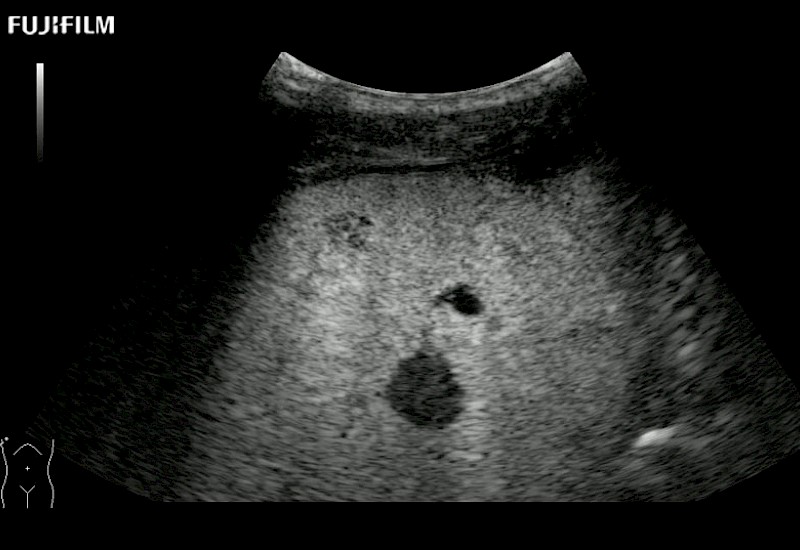

Our dedication to Surgical Oncology allows us to offer superior image quality, outstanding system reliability and intuitive use of cutting edge technology.

The ARIETTA 750 incorporates all of the proven technologies and functions that medical professionals have come to expect from Fujifilm Healthcare.

ARIETTA 750 is the definitive diagnostic ultrasound solution for any clinical setting - Private Office, Imaging Center, or Hospital. The ARIETTA platform provides the ultimate in clinical performance with its state-of-the-art features and large user-friendly display.

The ARIETTA 650 DI combines trusted Fujifilm Healthcare technologies and features tailored for surgical oncology.

Designed to meet the demands of surgeons, the ARIETTA 650 DI offers precise guidance. Its advanced capabilities and large, intuitive display offer accurate and efficient care in operating rooms and specialized surgical settings.